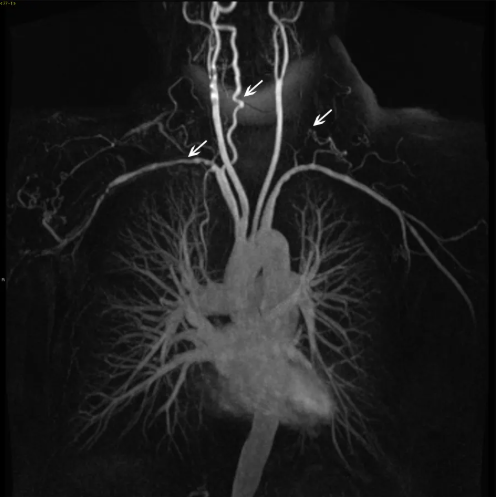

- HHT 환자는 주기적으로 혈액 검사, 영상 검사(예: CT, MRI)를 통해 AVM의 크기, 출혈 상태, 빈혈 여부 등을 확인해야 합니다.

- CT나 MRI를 이용해 동정맥루의 크기와 위치를 추적하는 것이 중요합니다.